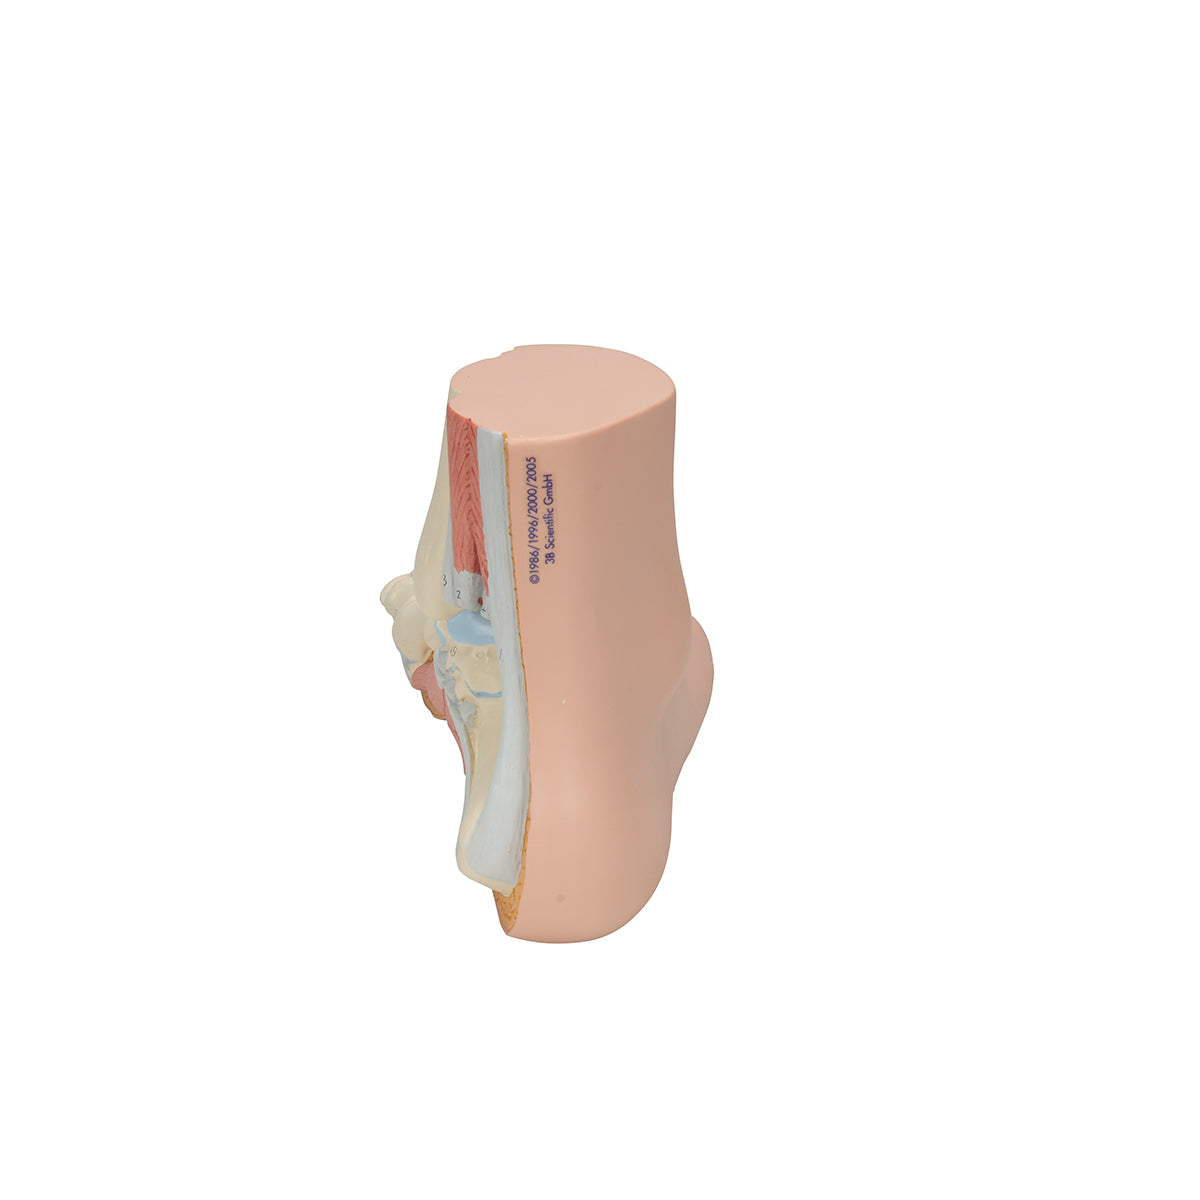

Pie Normal

Pie Normal

Tanto las estructuras superficiales como los huesos internos, músculos, ligamentos y nervios están enumerados según el texto explicativo correspondiente.

- Peso 0.44 kg

- Dimension 13 x 24 x 9 cm